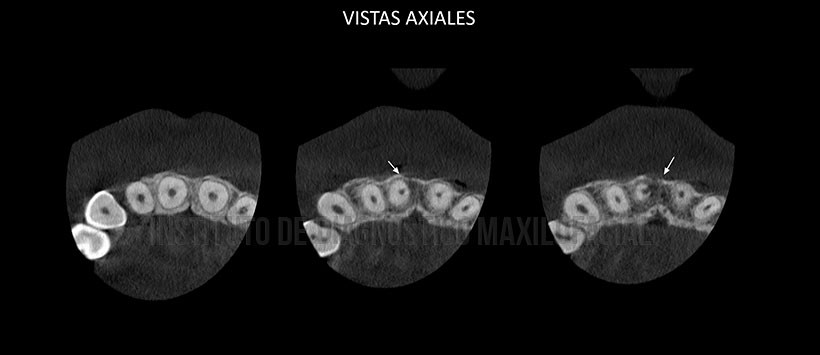

En la tomografía volumétrica de haz cónico localizada se aprecia, que la pieza 11 presenta cálculos pulpares (pulpolitos) así como una falta del cierre apical. En la pieza 21 al igual que su contraparte, se observan cálculos pulpares y falta de cierre apical sin embargo lo mas resaltante es el ensanchamiento del espacio del ligamento periodontal en zona apical lo que nos indica un posible proceso osteolítico en formación. (Figura 2, Figura 3 y Figura 4 )